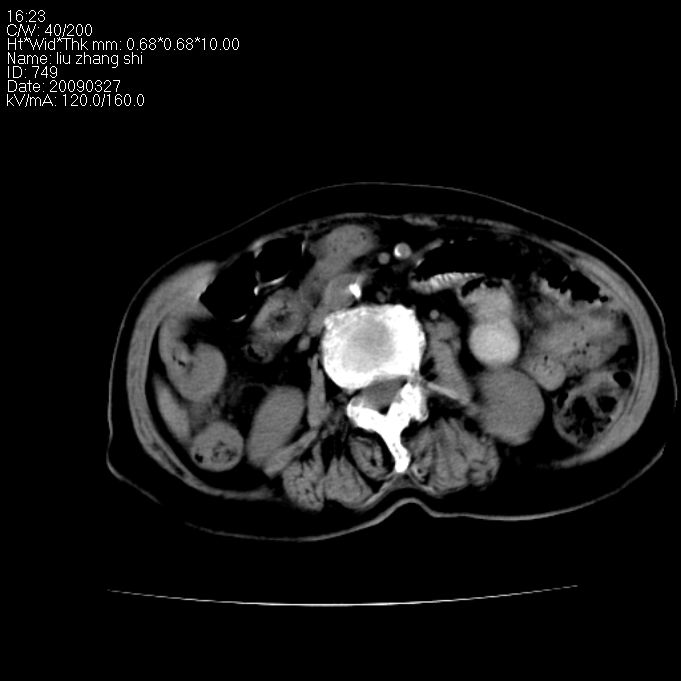

标题: CT19070:女 91岁 纳差 黄疸一月 [打印本页]

标题: CT19070:女 91岁 纳差 黄疸一月

1)胆系低位梗阻(肝内外胆管扩张,主胰管扩张,胆囊增大),原因待查;不排除壶腹癌所致可能。2)肝右叶后下段肝内胆管结石(或钙化)。

胰头【钩突】癌

胆系扩张,考虑壶腹部占位,肝门区占位考虑胆管癌

肝内胆管结石,肝总管肝内外胆管扩张,胆囊增大,胆总管胰头上部区占位【注意观察8,9两幅图像】--建议增强检查加mri 检查